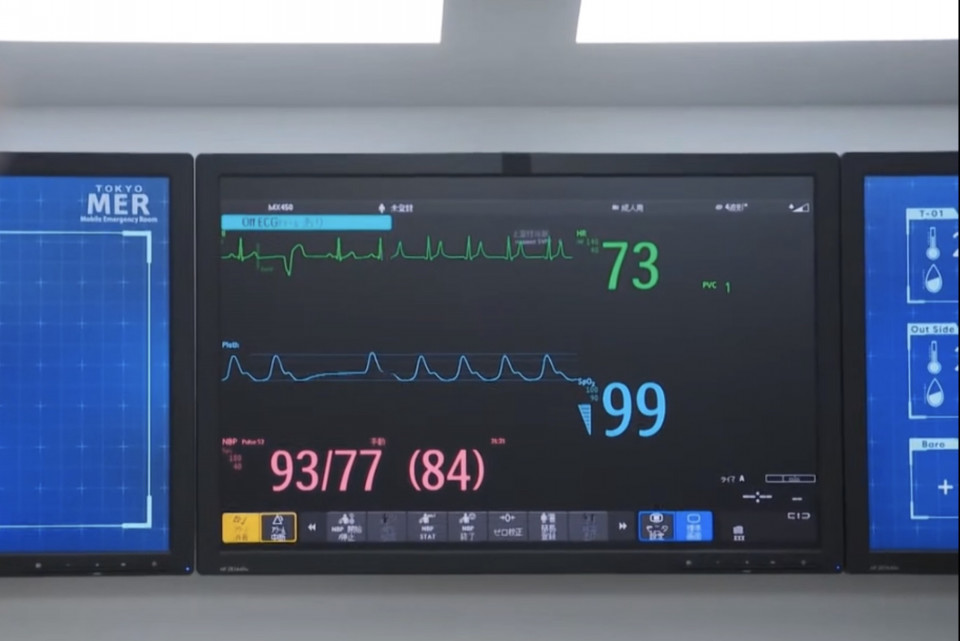

少女の症状

発汗

蕁麻疹

喘鳴(気道閉塞)

チアノーゼ

血圧低下など

上記アナフィラキシー症状あり